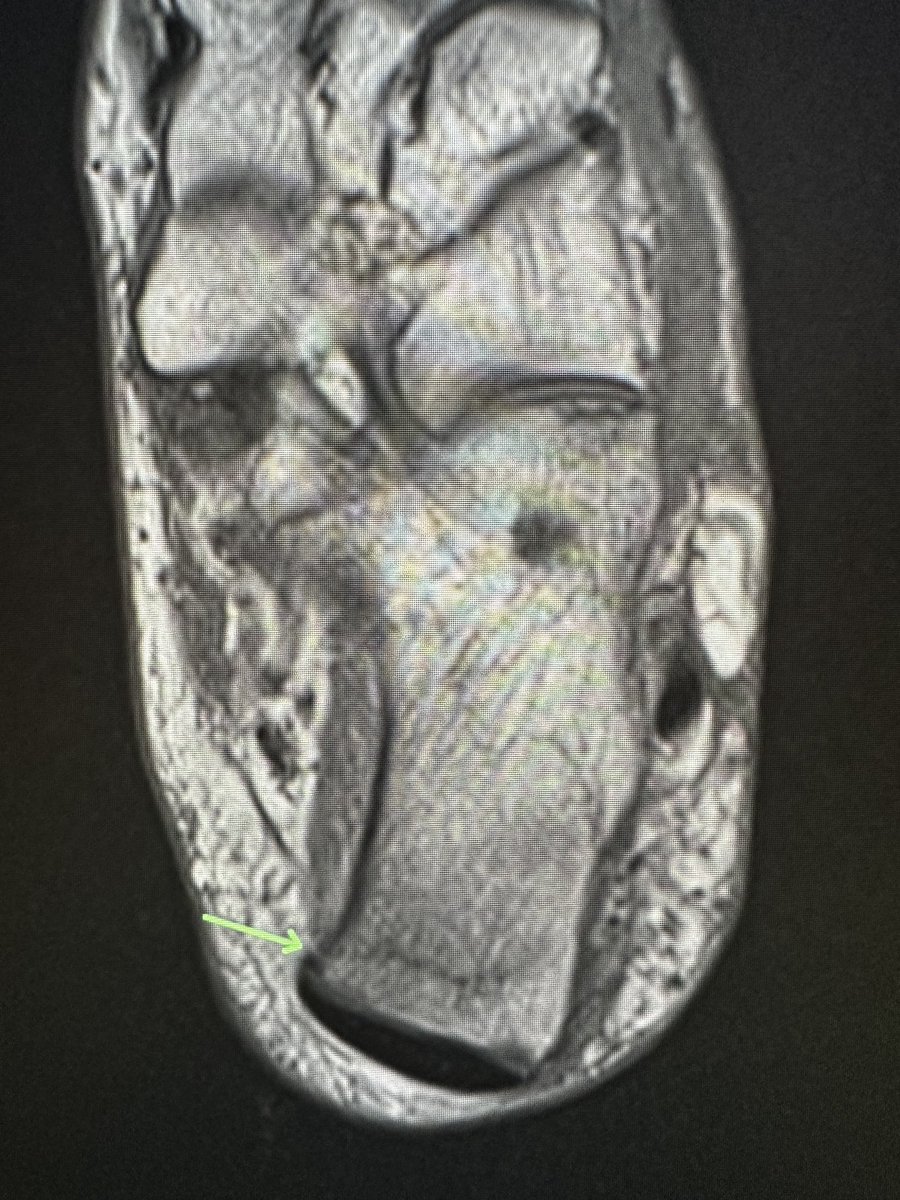

Gonzalo Serrano-Belmar.@GSERRANOB_MSK·

Cyclops injury. Also known as localized anterior arthrofibrosis, it is almost exclusively a complication of ACL reconstruction, with the appearance of an ovoid nodule most commonly located on the anterior aspect of the ACL graft near the tibial insertion. Risk factors female gender, greater graft volume, bone avulsion lesions, excessive anterior tibial tunnel, and double-bundle ACLR. This case is a 23-year-old man, a high-level athlete, with limited and painful terminal knee extension post-ACLR. The relationship of the cyclops lesion with the limitation of the knee extension during flexion-extension maneuvers can be observed. Undoubtedly, magnetic resonance imaging of the knee is the imaging study of choice. Still, dynamic ultrasound can be an excellent complement to demonstrate to the patient and treating physician its causality. #mskrad